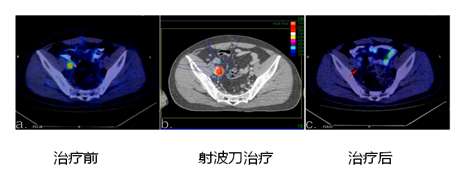

对于妇科肿瘤,结直肠癌癌放疗后髂脉管转移灶,传统放疗因为治疗精度差,肿瘤辐射抵抗,传统放疗难以再次给量,而射波刀对于髂脉管淋巴结转移有优异的局控效果,同时对于周围肠道,膀胱等组织的损伤较传统治疗都要小。对于骨盆转移,射波刀也有较好的局控作用。

图14 射波刀治疗髂脉管转移疗效(病灶治疗后消失,引自Wang ZQ, Zhuang HQ,et al.文章)